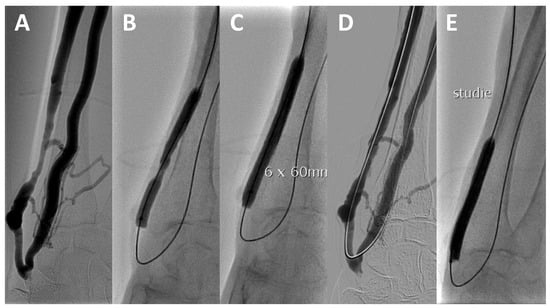

2.5. Trial Procedure